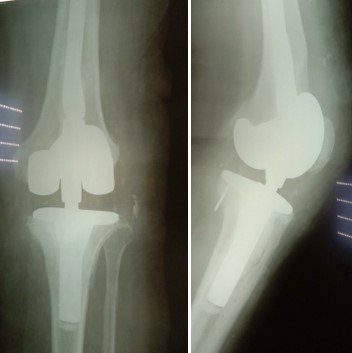

Приклад 1. Хвора Б. 52 років. Діагноз: Ревматоидній Деформівний IVст. гонартроз, вальгусна деформація колінногосуглоба.  Нестабільність та руйнування компонентів ендопротеза. Хворій виконано ревізійне ендопротезування: видалення компонентів ендопротезу, виявлений дефект латерального  виростку великогомілкової кістки тип Т3А за класифікацією АОRI [G.A. Engh, C.H. Rorabeck, 1997]. Під час операції виконана кісткова пластика дефекту латерального виростка лівої великогомілкової кістки. Використаний ендопротез колінного суглоба з подовжувачами .

Приклад 2. Хвора  М. 68 років. Діагноз: лівобічний деформівний IVст. гонартроз, стан після ТЕП лівого КС (2014р.). Під час виконання оперативного втручання компоненти ендопротезу встановлені в варусному положенні. Асептична нестабільність компонентів ендопротеза, тотальна  нестабільність зв’язкового апарату компонентів колінного суглоба (2017 р.)  Хворій виконано ревізійне ендопротезування: видалення компонентів ендопротезу, виявлений дефект виростку великогомілкової кістки тип Т2А за класифікацією АОRI [G.A. Engh, C.H. Rorabeck, 1997]. Враховуючи стан зв’язкового апарату використаний зв’язаний ендопротез типу Hinch.

Приклад 3. Хвора К. 52 років. Діагноз: Деформівний IVст. гонартроз, стан після ТЕП лівого КС (2013р.). ІМТ хворої складає 35 балів. Асептична нестабільність компонентів ендопротеза лівого колінного суглоба, міграція великогомілкового компоненту (2017 р.) (рис. 2 а). Хворій виконано ревізійне ендопротезування: видалення компонентів ендопротезу, виявлений дефект медіального виростку великогомілкової кістки тип Т3А за класифікацією АОRI [G.A. Engh, C.H. Rorabeck, 1997]. Під час операції виконана кісткова пластика дефекту. Використаний ендопротез колінного суглоба з подовжувачами.

Приклад 4. Хвора Г. 72 років. Діагноз: Деформівний IV ст. гонартроз, стан після ТЕП КС (2010р.). Гемартроз в післяопераційному періоді, хронічний синовііт.Септична нестабільність компонентів ендопротеза  колінного суглоба на протязі року. Виявлений дефект виростків стегнової кістки  тип Т3, F 3 за класифікацією АОRI [G.A. Engh, C.H. Rorabeck, 1997]. Хворій виконано  двоєтапне ревізійне ендопротезування: видалення компонентів ендопротезу іплантовано спейсер з антибіотиком. Піcля санаціїї виконано другий єтап певізії, імплантовано ревізійний ендопротез колінного суглоба.